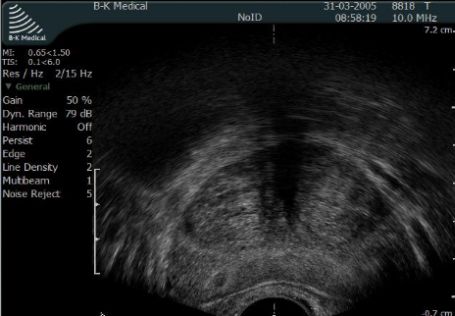

Objawy, które pan opisuje mogą być spowodowane ropniem gruczołu krokowego. Aby postawić rozpoznanie ropnia konieczne jest wykonanie transrektalnego USG gruczołu krokowego.

Fot. Przekrój poprzeczny gruczołu krokowego w USG transrektalnym.